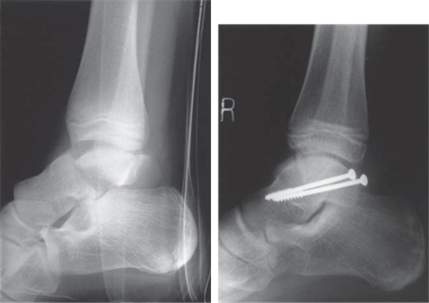

Describe what you see in this picture and explain your initial management.

This is an AP radiograph of the left ankle showing a multifragmentary pilon fracture.

I would perform an ATLS review and rule out concomitant injuries. I would then assess the neurovascular status of the aff ected limb and observe for signs of open injury or degloving. I would apply a temporary splint, provide analgesia, and obtain AP and lateral radiographs.

What is your primary treatment upon admission?

I would commence monitoring for signs of compartment syndrome. I would plan to take the patient to theatre and place a spanning external fi xator. This would keep the limb out to length, maintain alignment, and most importantly avoid further insult to the soft tissues.